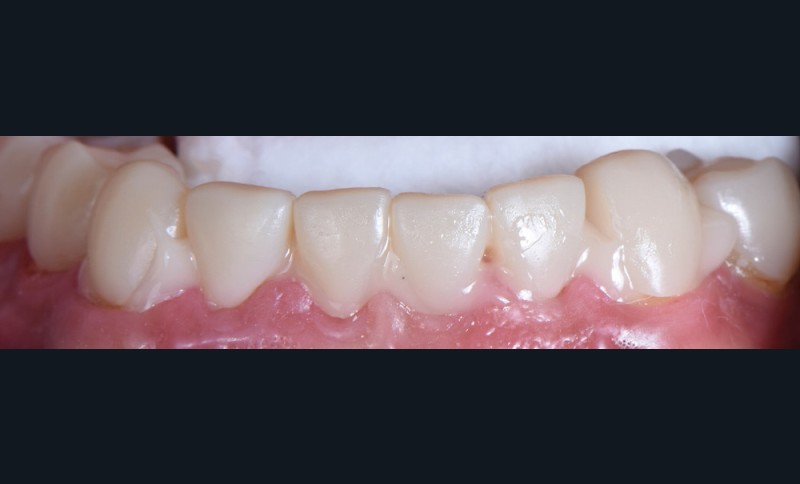

Au vu du contexte para-fonctionnel et de l’étendue de la perte tissulaire, des coiffes périphériques minimalement invasives ont été choisies afin de restaurer l’esthétique et la fonction. Actuellement, aucun consensus n’est fait sur le choix du matériau d’infrastructure à privilégier. Les matériaux hybrides usinables présentent des propriétés mécaniques, physiques et biologiques intéressantes en contexte d’usure sévère (e.g., module d’élasticité, résistance à la propagation de fêlures, facilité de réintervention). Une réhabilitation globale avec remontée de dimension verticale d’occlusion (DVO) par l’intermédiaire de coiffes composites renforcés en nano-céramiques est décrite.